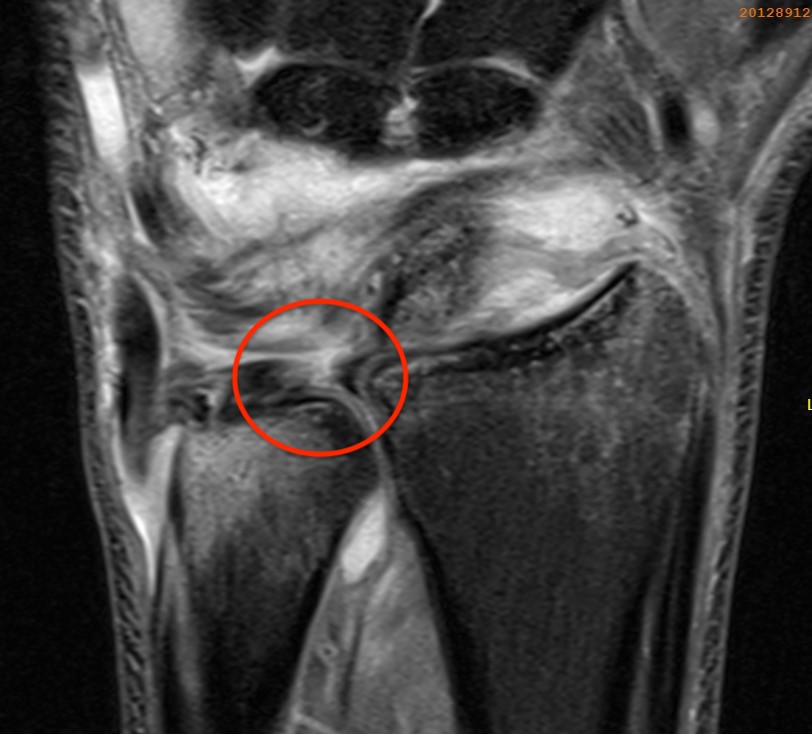

Ulno-carpal abutment

Ulnocarpal abutment and lunate chondromalacia

Central TFCC tear with ulna positive variance an ulnocarpal abutment on MRI

Ulna impaction syndrome / Ulno-carpal abutment

Progression of wear

- TFCC thinning

- ulna head and lunate cartilage wear

- TFCC perforation

- lunate-triquetral ligament injury

- ulnocarpal osteoarthritis

Usually associated with ulna positive variance and treated with ulna shortening